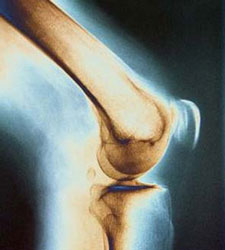

وی افزود: هنگامی که خونرسانی به عضو از بین میرود و عضو از انتها شروع به سیاه شدن میکند، نکروز استخوانی ایجاد میشود و ممکن است استخوان سر ران پا یا سایر استخوانها را درگیر کند.

نیکو خاطرنشان کرد: برای درمان نکروز استخوان سر ران باید عمل جراحی انجام شود و به جای استخوان سیاه شده، پروتز گذاشته شود.